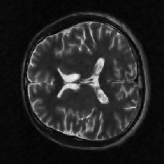

4.1 Phantom experiments

For the piecewise constant phantom experiments, we first compute the fully sampled k-space data using Eq. 3.1 with a piecewise constant function model Eq. 3.6. More precisely, given that ΩjsubscriptΩ𝑗\Omega_{j}’s are ellipses, Eq. 3.6 can be explicitly written as

where J1subscript𝐽1J_{1} is the first kind Bessel’s function of order 111. Then using the variable density random sampling method in [46], we generate 20%percent2020\% undersampled k-space data. The complex white Gaussian noise is also added so that the resulting SNR of the samples is approximately 25dB25dB25\mathrm{dB} (See Fig. 3).

Refer to caption

(a) Fully sampled

(b) Ground truth

(c) Sample mask

(d) Undersampled

Figure 3: Dataset for the phantom experiments. Fully sampled k-space data, its inverse DFT as a ground truth, the undersampling mask, and the undersampled k-space data.